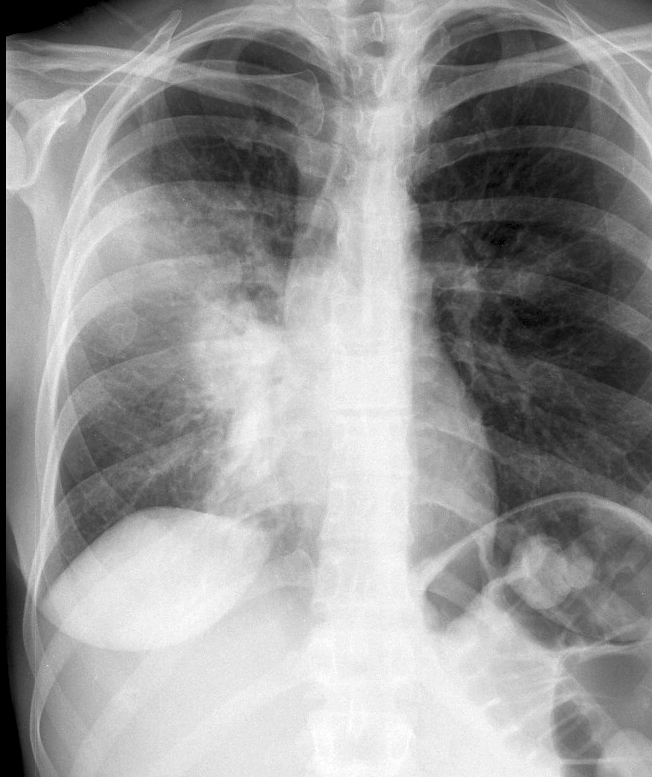

Case 3 RM & UL pneum PA